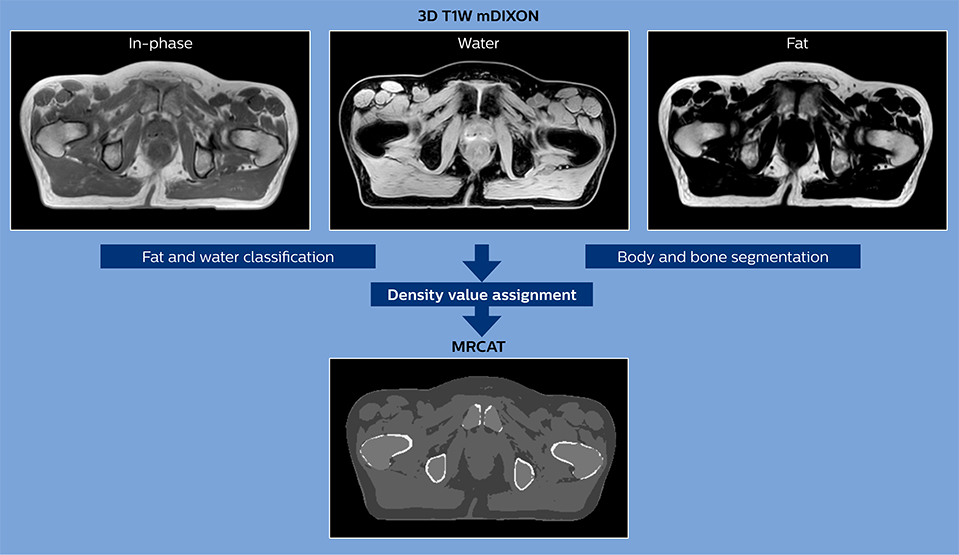

The 3D T1W FFE mDIXON sequence provides in-phase, water and fat images in one acquisition. Target and organs-at-risk are delineated on the 3D T2W TSE images. Prostate GTV is shown in orange, PTV in purple. The 3D bFFE sequence is used by the planner to mark the position of the fiducial markers (gold anchors) and contours are transferred to the digitally reconstructed radiographs (DRRs).

Based on the 3D T1W mDIXON images, MR-based density maps (MRCAT) are automatically generated. The VMAT (Volumetric Modulated Arc Therapy) plan is generated in TPS, based on MRCAT as primary image set. During the commissioning phase, dosimetric agreement between MRCAT-based and CT-based dose plans was studied and differences in the PTV dose were found to be minimal (<1% for most patients). Average difference in PTV mean values was 0.8% over the study group (n=62).

How does MRCAT generation work?

The Philips MRCAT approach for an MR-only based dose planning provides CT-like density information calculated from MR images for dose calculations, as well as high contrast anatomical T2W images for target delineation. [2-3]

Electron density information is automatically generated on the MR console from a single T1W mDIXON MRI sequence in two steps:

1. MR image contents are categorized into air, fat, water-rich tissue, spongy bone and compact bone using a hybrid approach of image and model-based segmentation.

2. Each voxel is assigned a density value (pseudo-HU value, where HU stands for Hounsfield Unit), based on a combination of average population values and literature values.

The MRCAT images with density information are DICOM conform and can be automatically exported to treatment planning systems (TPS) as primary image dataset for dose calculations and to generate MR-based digitally reconstructed radiographs (DRRs).